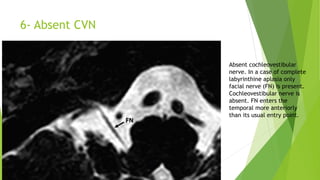

6- Absent CVN

Absent cochleovestibular

nerve. In a case of complete

labyrinthine aplasia only

facial nerve (FN) is present.

Cochleovestibular nerve is

absent. FN enters the

temporal more anteriorly

than its usual entry point.